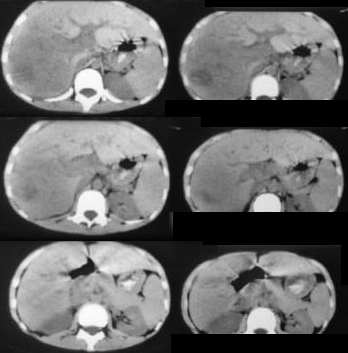

肝母细胞瘤(hb)好发年龄在3岁以下,以1岁以下为多见,与乙型病毒性肝硬化无关,90%以上甲胎蛋白阳性明显升高,钙化占肿瘤38%~50%,由于肝母细胞瘤生长迅速,在肿瘤区域可出现不同程度坏死、出血或纤维瘢痕。

肝细胞癌 发病年龄高峰为4岁及12~15岁,男女之比约为1.3,与hbv感染、肝硬化有关。组织形态上,分化好的肝细胞癌可见到一些肝细胞的特征。

本例考虑肝细胞癌

下面上传经病理证实的hb